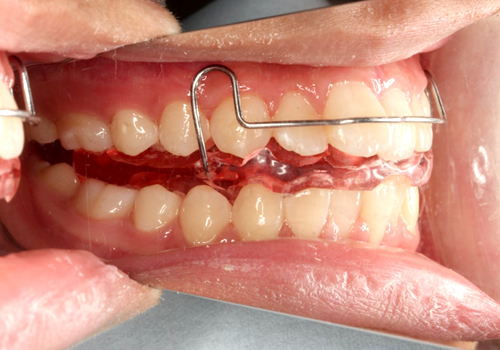

症例05. EF-line

ビニール製やゴム製のマウスピース様装置です。咬合様式に合った様々なタイプがあり、噛んでいただくことで咬合誘導や歯列拡大を行います。舌癖の是正も期待できます。

| 治療内容 | 1:舌突出に伴う出っ歯さん 2:正しい位置で噛むことを習慣づける 3:あごと舌の正しい位置を覚えてもらう |

|---|---|

| 期間 | 1年~2年 |

| 費用 | 300,000円+税 |

| リスク | 慣れないうちは多少の息苦しさもありますが、鼻呼吸を促し問題も解決されていきます。 |